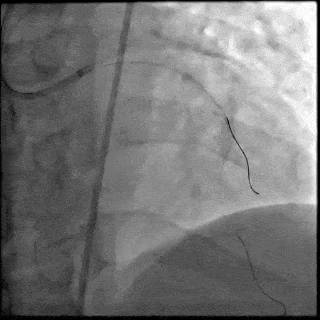

【DSA图 前降支支架释放】

5月28日8:00,葛均波院士团队在中山医院16号楼16楼中伟厅成功连线喀什二院导管室,沪喀远程手术正式开始。8:35,新疆喀什二院导管室内股动脉入路通路建立后,行左右冠脉造影示左前降支中段存在85%的严重狭窄,狭窄位于血管分叉路口且紧邻心肌桥;且左回旋支中段近乎闭塞,血管细窄且迂曲,病变弥漫。8:59,葛院士于上海操控血管介入机器人主端PANVIS COF,将指引导管送至左冠脉开口,并操控主支导丝和分支血管保护导丝通过狭窄病变,后送至前降支和对角支血管远端以建立轨道,同时利用介入机器人的微速调整功能避开心肌桥,以亚毫米级精准定位释放1枚支架。在成功处理患者左前降支病变后,葛院士通过搓捻机械操纵杆,远程精细调整导丝“进攻”方向,顺利通过左回旋支次全闭塞病变。因血管相对细小且病变弥漫,葛院士决定采用单纯球囊扩张术处理,即刻造影提示几乎无残余狭窄,避免了额外的支架植入。10:10,撤出所有导丝及导管,手术顺利结束。